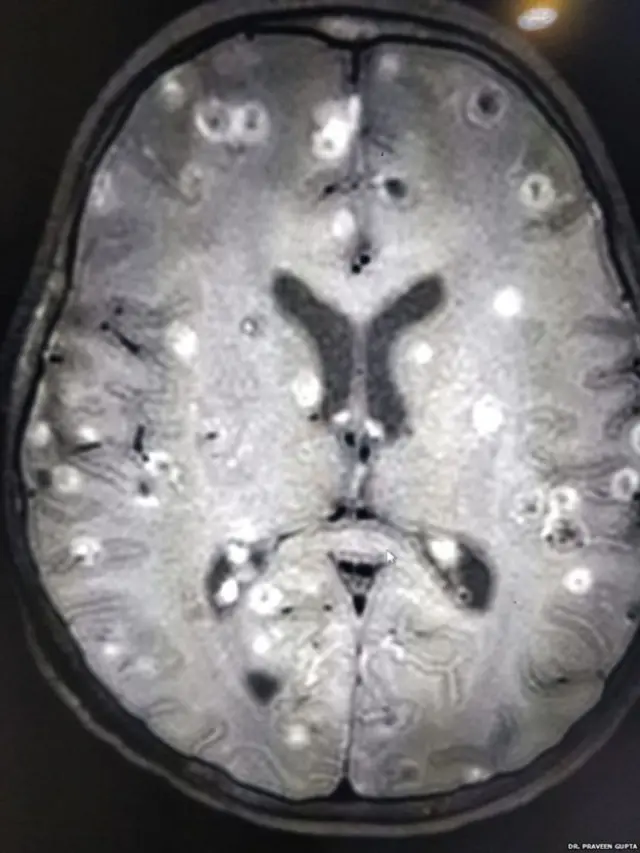

"சிறுமியின் மூளைக்குள் 100க்கும் மேற்பட்ட நாடாப்புழுக்களின் முட்டைகள் இருந்தன. அவை சிறு சிறு கட்டிகளைப்போல் காணப்பட்டன," என்று கூறுகிறார் மருத்துவர் பிரவீண் குப்தா.

டெல்லிக்கு அருகில் குருகிராமில் பிரபலமான ஒரு மருத்துவமனையில் நரம்பியல் துறை தலைவர் மருத்துவர் பிரவீண் குப்தாவின் கண்காணிப்பில் சிறுமிக்கு சிகிச்சை நடைபெறுகிறது.

பட மூலாதாரம், DR PRAVEEN GUPTA

சிகிச்சைக்காக தன்னிடம் அழைத்து வரப்பட்ட சிறுமிக்கு சி.டி ஸ்கேன் எடுத்துப் பார்த்த குப்தா, அவர் நியூரோசிஸ்டிசிரோசிஸ் (Neurocysticercosis) என்ற நோயால் பாதிக்கப்பட்டிருப்பதை கண்டறிந்தார்.

"மருத்துவமனைக்கு கொண்டுவரப்பட்டபோது சிறுமி மயக்கநிலையில் இருந்தார். அவரது மூளையில் நூற்றுக்கணக்கான வெண்ணிற புள்ளிகள் இருப்பதை சி.டி ஸ்கேன் காட்டியது. அவை என்ன தெரியுமா? நாடாப்புழுவின் முட்டைகள்."